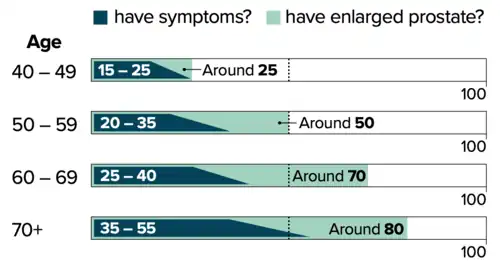

As of 2019, about 94 million men aged 40 years and older are affected globally.[3] BPH typically begins after the age of 40.[1] The prevalence of clinically diagnosed BPH peaks at 24% in men aged 75–79 years.[3] Based on autopsy studies, half of males aged 50 and over are affected, and this figure climbs to 80% after the age of 80.[3] Although prostate specific antigen levels may be elevated in males with BPH, the condition does not increase the risk of prostate cancer.[8]

The prostate gets larger in most men as they get older. For a symptom-free man of 46 years, the risk of developing BPH over the next 30 years is 45%. Incidence rates increase from 3 cases per 1000 man-years at age 45–49 years, to 38 cases per 1000 man-years by the age of 75–79 years. While the prevalence rate is 2.7% for men aged 45–49, it increases to 24% by the age of 80 years.[169]